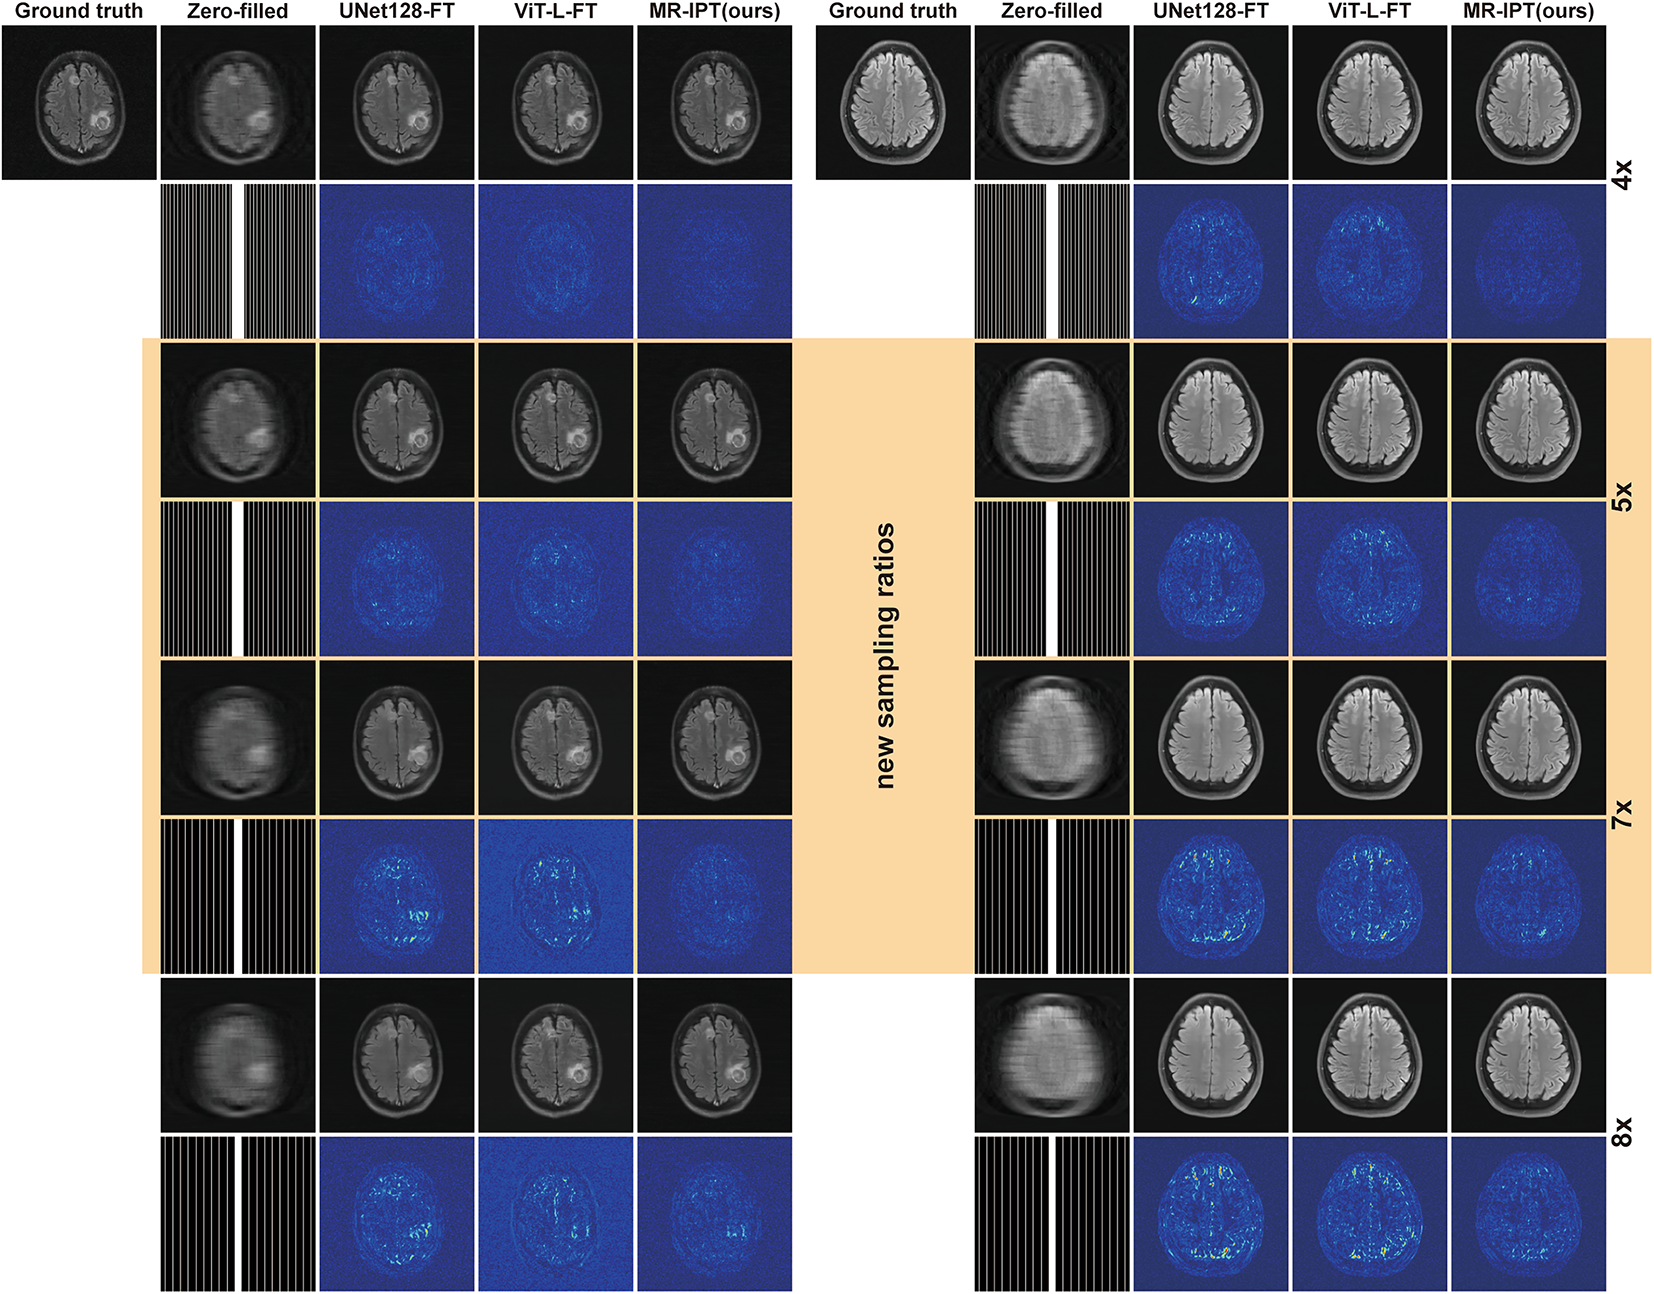

Fig. 4

Restoration comparison across multiple sampling ratios, including unseen configurations. This figure showcases the performance of different models in reconstructing MRI images at various acceleration ratios. Results highlighted in the yellow block represent new sampling ratios (e.g., 5× and 7×) that were not encountered during pre-training, demonstrating each model’s generalization ability. The results highlight MR-IPT’s strong adaptability to previously unseen acceleration factors, effectively preserving fine anatomical structures while minimizing artifacts, compared to other baseline methods.